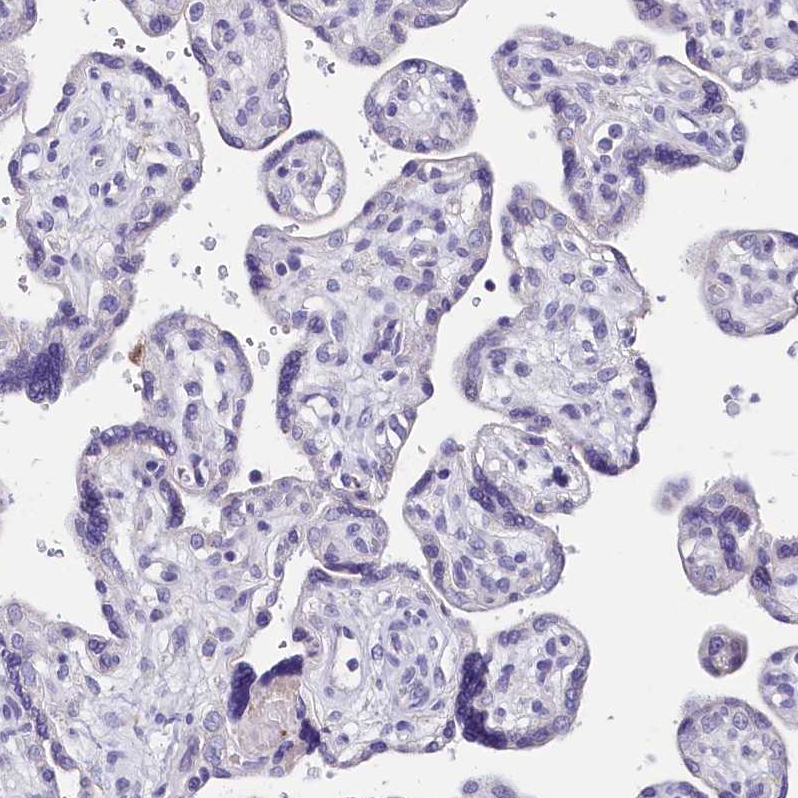

Immunohistochemical staining of human colon shows strong cytoplasmic positivity in glandular cells.